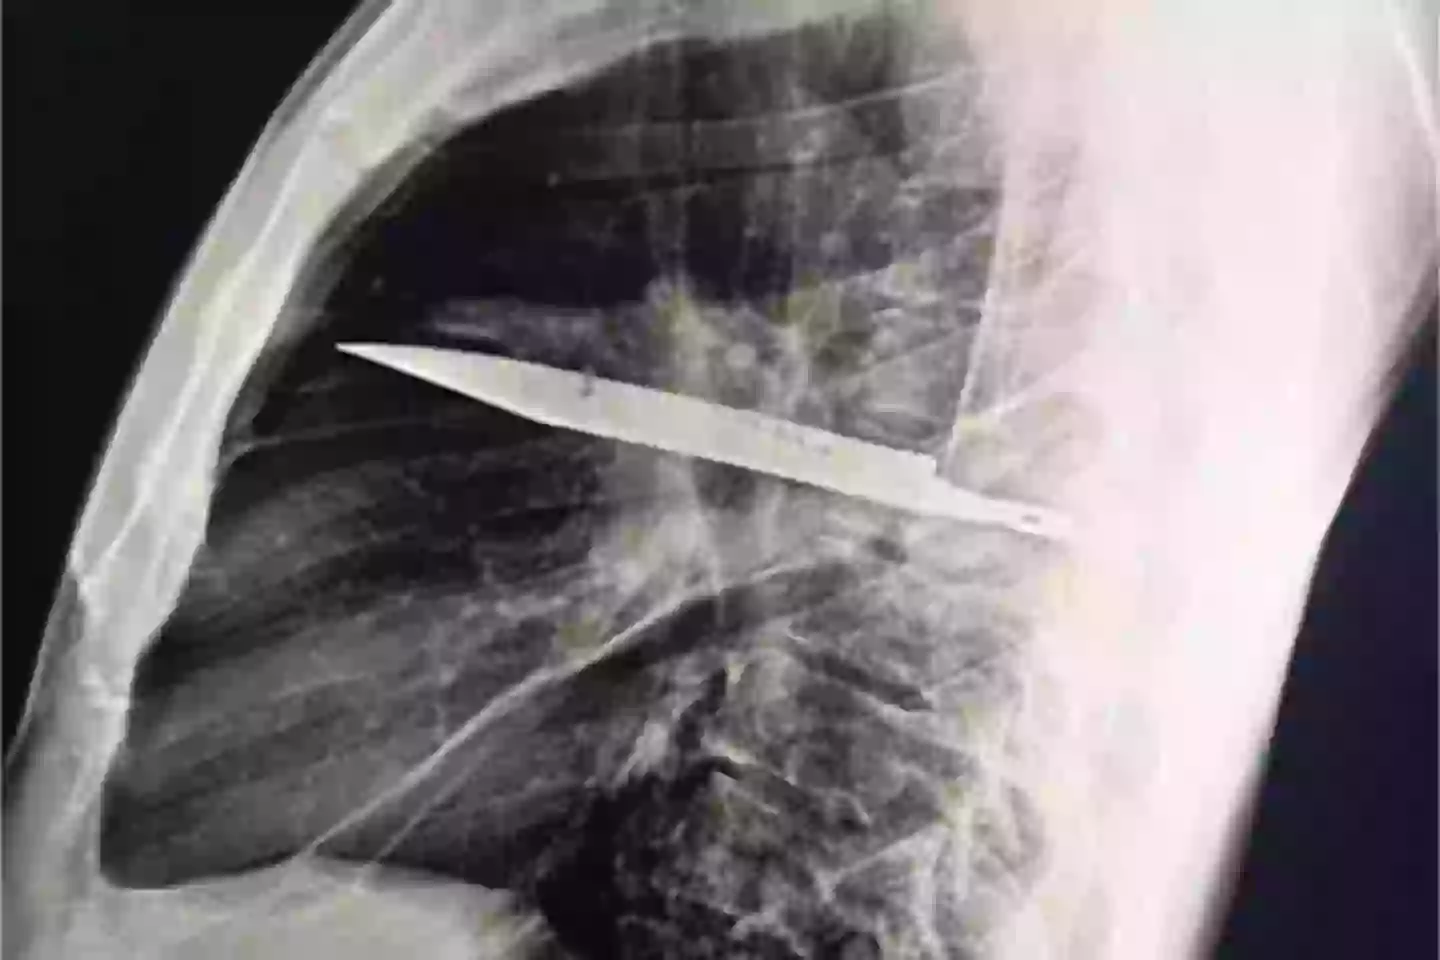

Sometimes truth is stranger than fiction, after an X-ray revealed the man had a sizeable knife buried deep inside his chest.

After ordering an X-ray, a ‘retained metallic object’ was found, and medics realised it was a knife, and it was surrounded by ‘pus and necrotic tissue’.

It had entered his body through his right shoulder.

The man was found to have a knife embedded in his chest (National Library of Medicine)